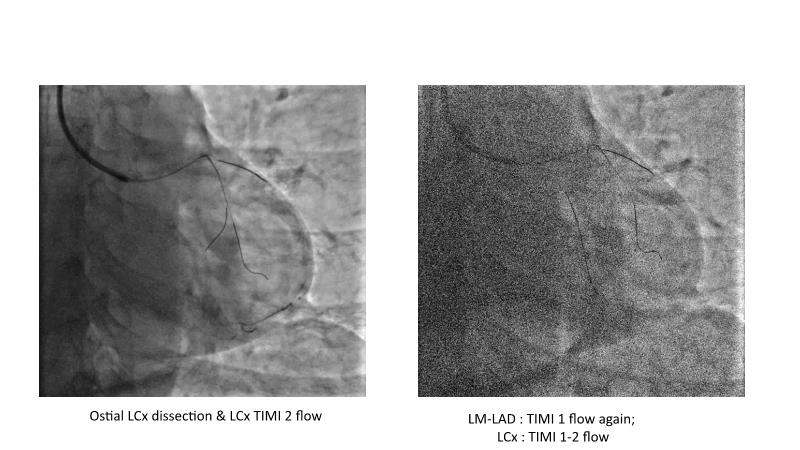

This session is recommended for you if you are seeking insights into the advantages of using IVUS imaging over visual assessment for better outcomes in left main bifurcation procedures. Discuss with experts the benefits of using RotaCUT in lesion preparation for left main bifurcation and explore the impact of high radial strength stents on the procedure's success.